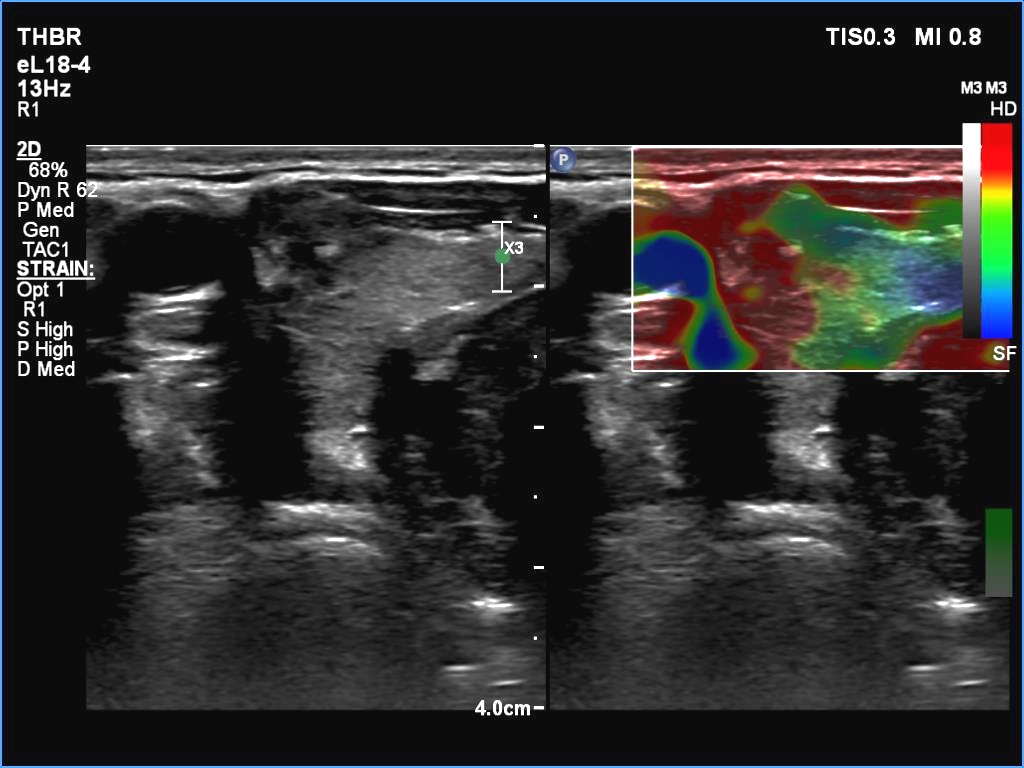

Ultrasonography. The thyroid was echonormal. There were two partly deeply hypoechoic nodules, one in the ventrolateral part of the right lobe and another one in the isthmus. Both had irregular margins and punctate echogenic foci. There was a mirror image artifact of the lesion in the isthmus.

Both nodules had multiple suspicious features: beside deep hypoechogenicity and irregular borders, microcalcifications should be also considered. The nodule in the right lobe presented also three possible sonographic signs of a possible extrathyroidal spread: the pseudocapsule of the thyroid was not intact, the lesion had both abutting and butting contours.